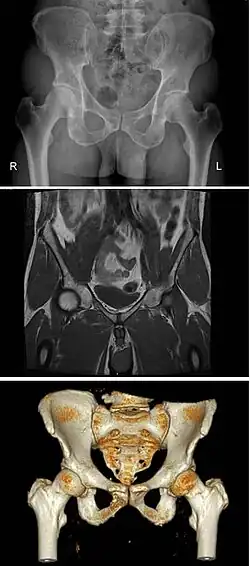

The pelvis (pl.: pelves or pelvises) is the lower part of an anatomical trunk,[1] between the abdomen and the thighs (sometimes also called pelvic region), together with its embedded skeleton[2] (sometimes also called bony pelvis or pelvic skeleton).

The pelvic region of the trunk includes the bony pelvis, the pelvic cavity (the space enclosed by the bony pelvis), the pelvic floor, below the pelvic cavity, and the perineum, below the pelvic floor.[1] The pelvic skeleton is formed in the area of the back, by the sacrum and the coccyx and anteriorly and to the left and right sides, by a pair of hip bones.

The two hip bones connect the spine with the lower limbs. They are attached to the sacrum posteriorly, connected to each other anteriorly, and joined with the two femurs at the hip joints. The gap enclosed by the bony pelvis, called the pelvic cavity, is the section of the body underneath the abdomen and mainly consists of the reproductive organs and the rectum, while the pelvic floor at the base of the cavity assists in supporting the organs of the abdomen.

In mammals, the bony pelvis has a gap in the middle, significantly larger in females than in males. Their offspring pass through this gap when they are born.

A distinction is made between the lesser or true pelvis inferior to the terminal line, and the greater or false pelvis above it. The pelvic inlet or superior pelvic aperture, which leads into the lesser pelvis, is bordered by the promontory, the arcuate line of ilium, the iliopubic eminence, the pecten of the pubis, and the upper part of the pubic symphysis. The pelvic outlet or inferior pelvic aperture is the region between the subpubic angle or pubic arch, the ischial tuberosities and the coccyx. [3]

Modern humans are to a large extent characterized by bipedal locomotion and large brains. Because the pelvis is vital to both locomotion and childbirth, natural selection has been confronted by two conflicting demands: a wide birth canal and locomotion efficiency, a conflict referred to as the "obstetrical dilemma". The female pelvis, or gynecoid pelvis,[8] has evolved to its maximum width for childbirth—a wider pelvis would make human females unable to walk. In contrast, human male pelvises are not constrained by the need to give birth and therefore are more optimized for bipedal locomotion.[9]

The principal differences between male and female true and false pelvis include:

- The female pelvis is larger and broader than the male pelvis which is taller, narrower, and more compact.[10] The female pelvis is lighter and thinner than the male pelvis.[11]

- The female inlet is larger and oval in shape, while the male sacral promontory projects further (i.e. the male inlet is more heart-shaped).[10]

- The sides of the male pelvis converge from the inlet to the outlet, whereas the sides of the female pelvis are wider apart.[12]

- The angle between the inferior pubic rami is acute (70 degrees) in males, but obtuse (90–100 degrees) in females. Accordingly, the angle is called subpubic angle in males and pubic arch in females.[10] Additionally, the bones forming the angle/arch are more concave in females but straight in males.[13]

- The distance between the ischia bones is small in males, making the outlet narrow, but large in females, who have a relatively large outlet. The ischial spines and tuberosities are heavier and project farther into the pelvic cavity in males. The greater sciatic notch is wider in females.[13]

- The iliac crests are higher and more pronounced in males, making the male false pelvis deeper and more narrow than in females.[13]

- The male sacrum is long, narrow, more straight, and has a pronounced sacral promontory. The female sacrum is shorter, wider, more curved posteriorly, and has a less pronounced promontory.[13]

- The acetabula are wider apart in females than in males.[13] In males, the acetabulum faces more laterally, while it faces more anteriorly in females. Consequently, when males walk the leg can move forwards and backwards in a single plane. In females, the leg must swing forward and inward, from where the pivoting head of the femur moves the leg back in another plane. This change in the angle of the femoral head gives the female gait its characteristic (i.e. swinging of hips).[14]